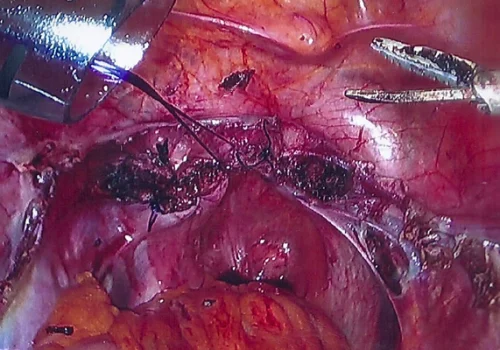

Procedure

She subsequently underwent Total Laparoscopic Hysterectomy and removal of both Fallopian Tubes and Ovaries. The uterus weighed 670g.